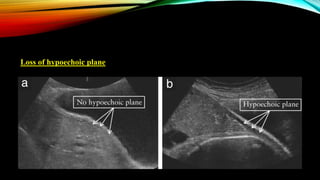

Loss of hypoechoic plane

• Loss of normal hypoechoic retroplacental zone.